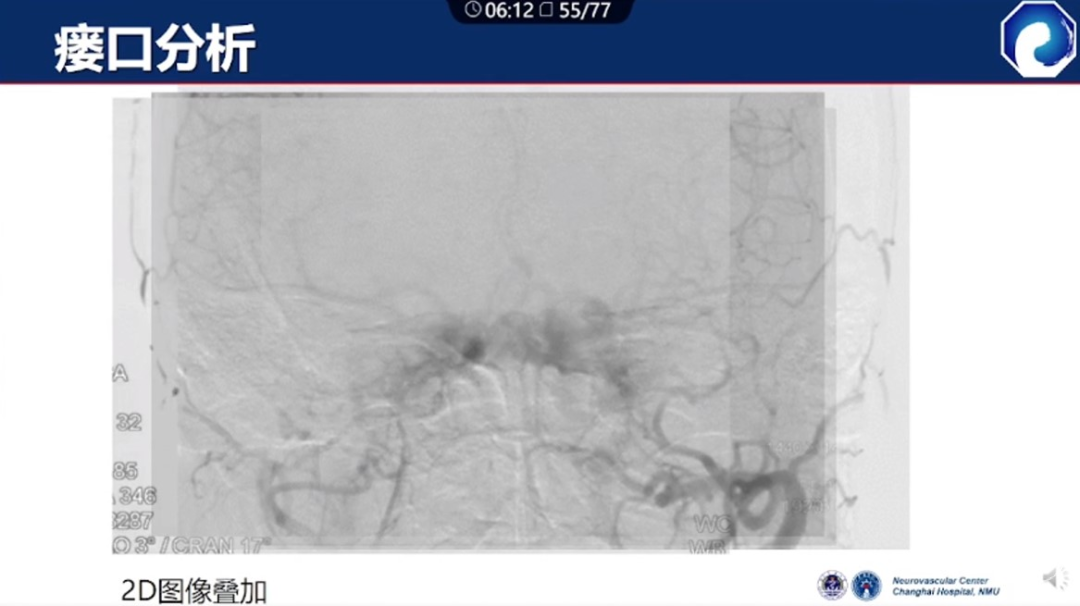

痿口静脉端的识别至关重要。

痿口静脉端精准完全闭塞是DAVF治愈的关键。